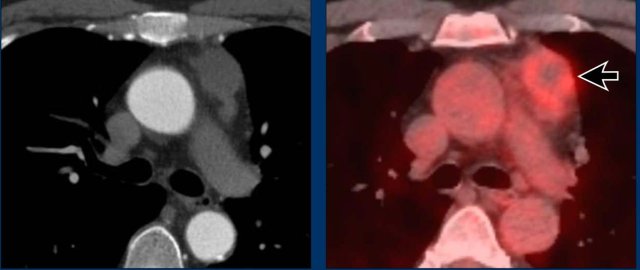

These images are of a 60-year old female.

She had cardiac arythmias and on a chest CT an incidental mass was seen.

First study the images.

Question: what is the most likely diagnosis?

Images

The mass has a high density on the post contrast scan.

There is no macroscopic fat.

The border is somewhat irregular.

And there is a second mass (arrow). On other levels more masses were seen.

Discussion

When there are multiple masses the most likely diagnosis is a lymphoma.

Whenever lymphoma is in your differential diagnosis, you need tissue sampling and you want to start chemotherapy as soon as you know what kind of lymphoma it is.